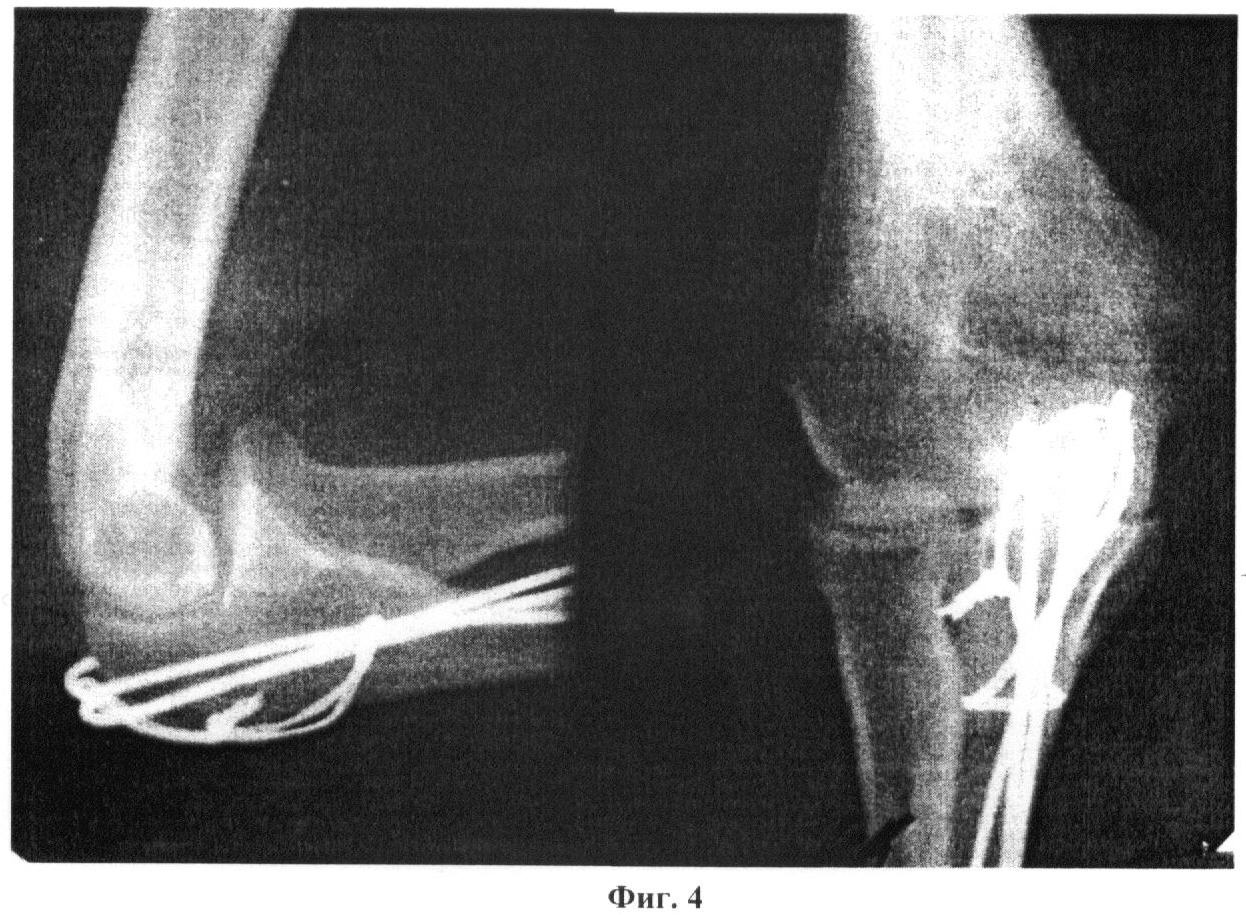

Пациент С., 45 лет. Диагноз: закрытый перелом правого локтевого отростка со смещением отломков. На фиг.2 представлена рентгенограмма до операции. Произведена открытая репозиция перелома, в соответствии с предложенным способом введены спицы Киршнера и стягивающая проволочная петля (на фиг.3 представлена рентгенограмма после операции). Через 4 дня после операции начата активная лечебная физкультура. На 10 день после операции пациент выписан на амбулаторное лечение с возможностью самообслуживания поврежденной конечностью. Через четыре недели после операции контрольной рентгенографией выявлено сращение перелома, отсутствие признаков миграции металлоконструкций (фиг.4). Достигнут хороший функциональный результат: мышечная сила в правой руке - 4 балла по пятибалльной системе, пассивные движения в правом локтевом суставе в полном объеме.